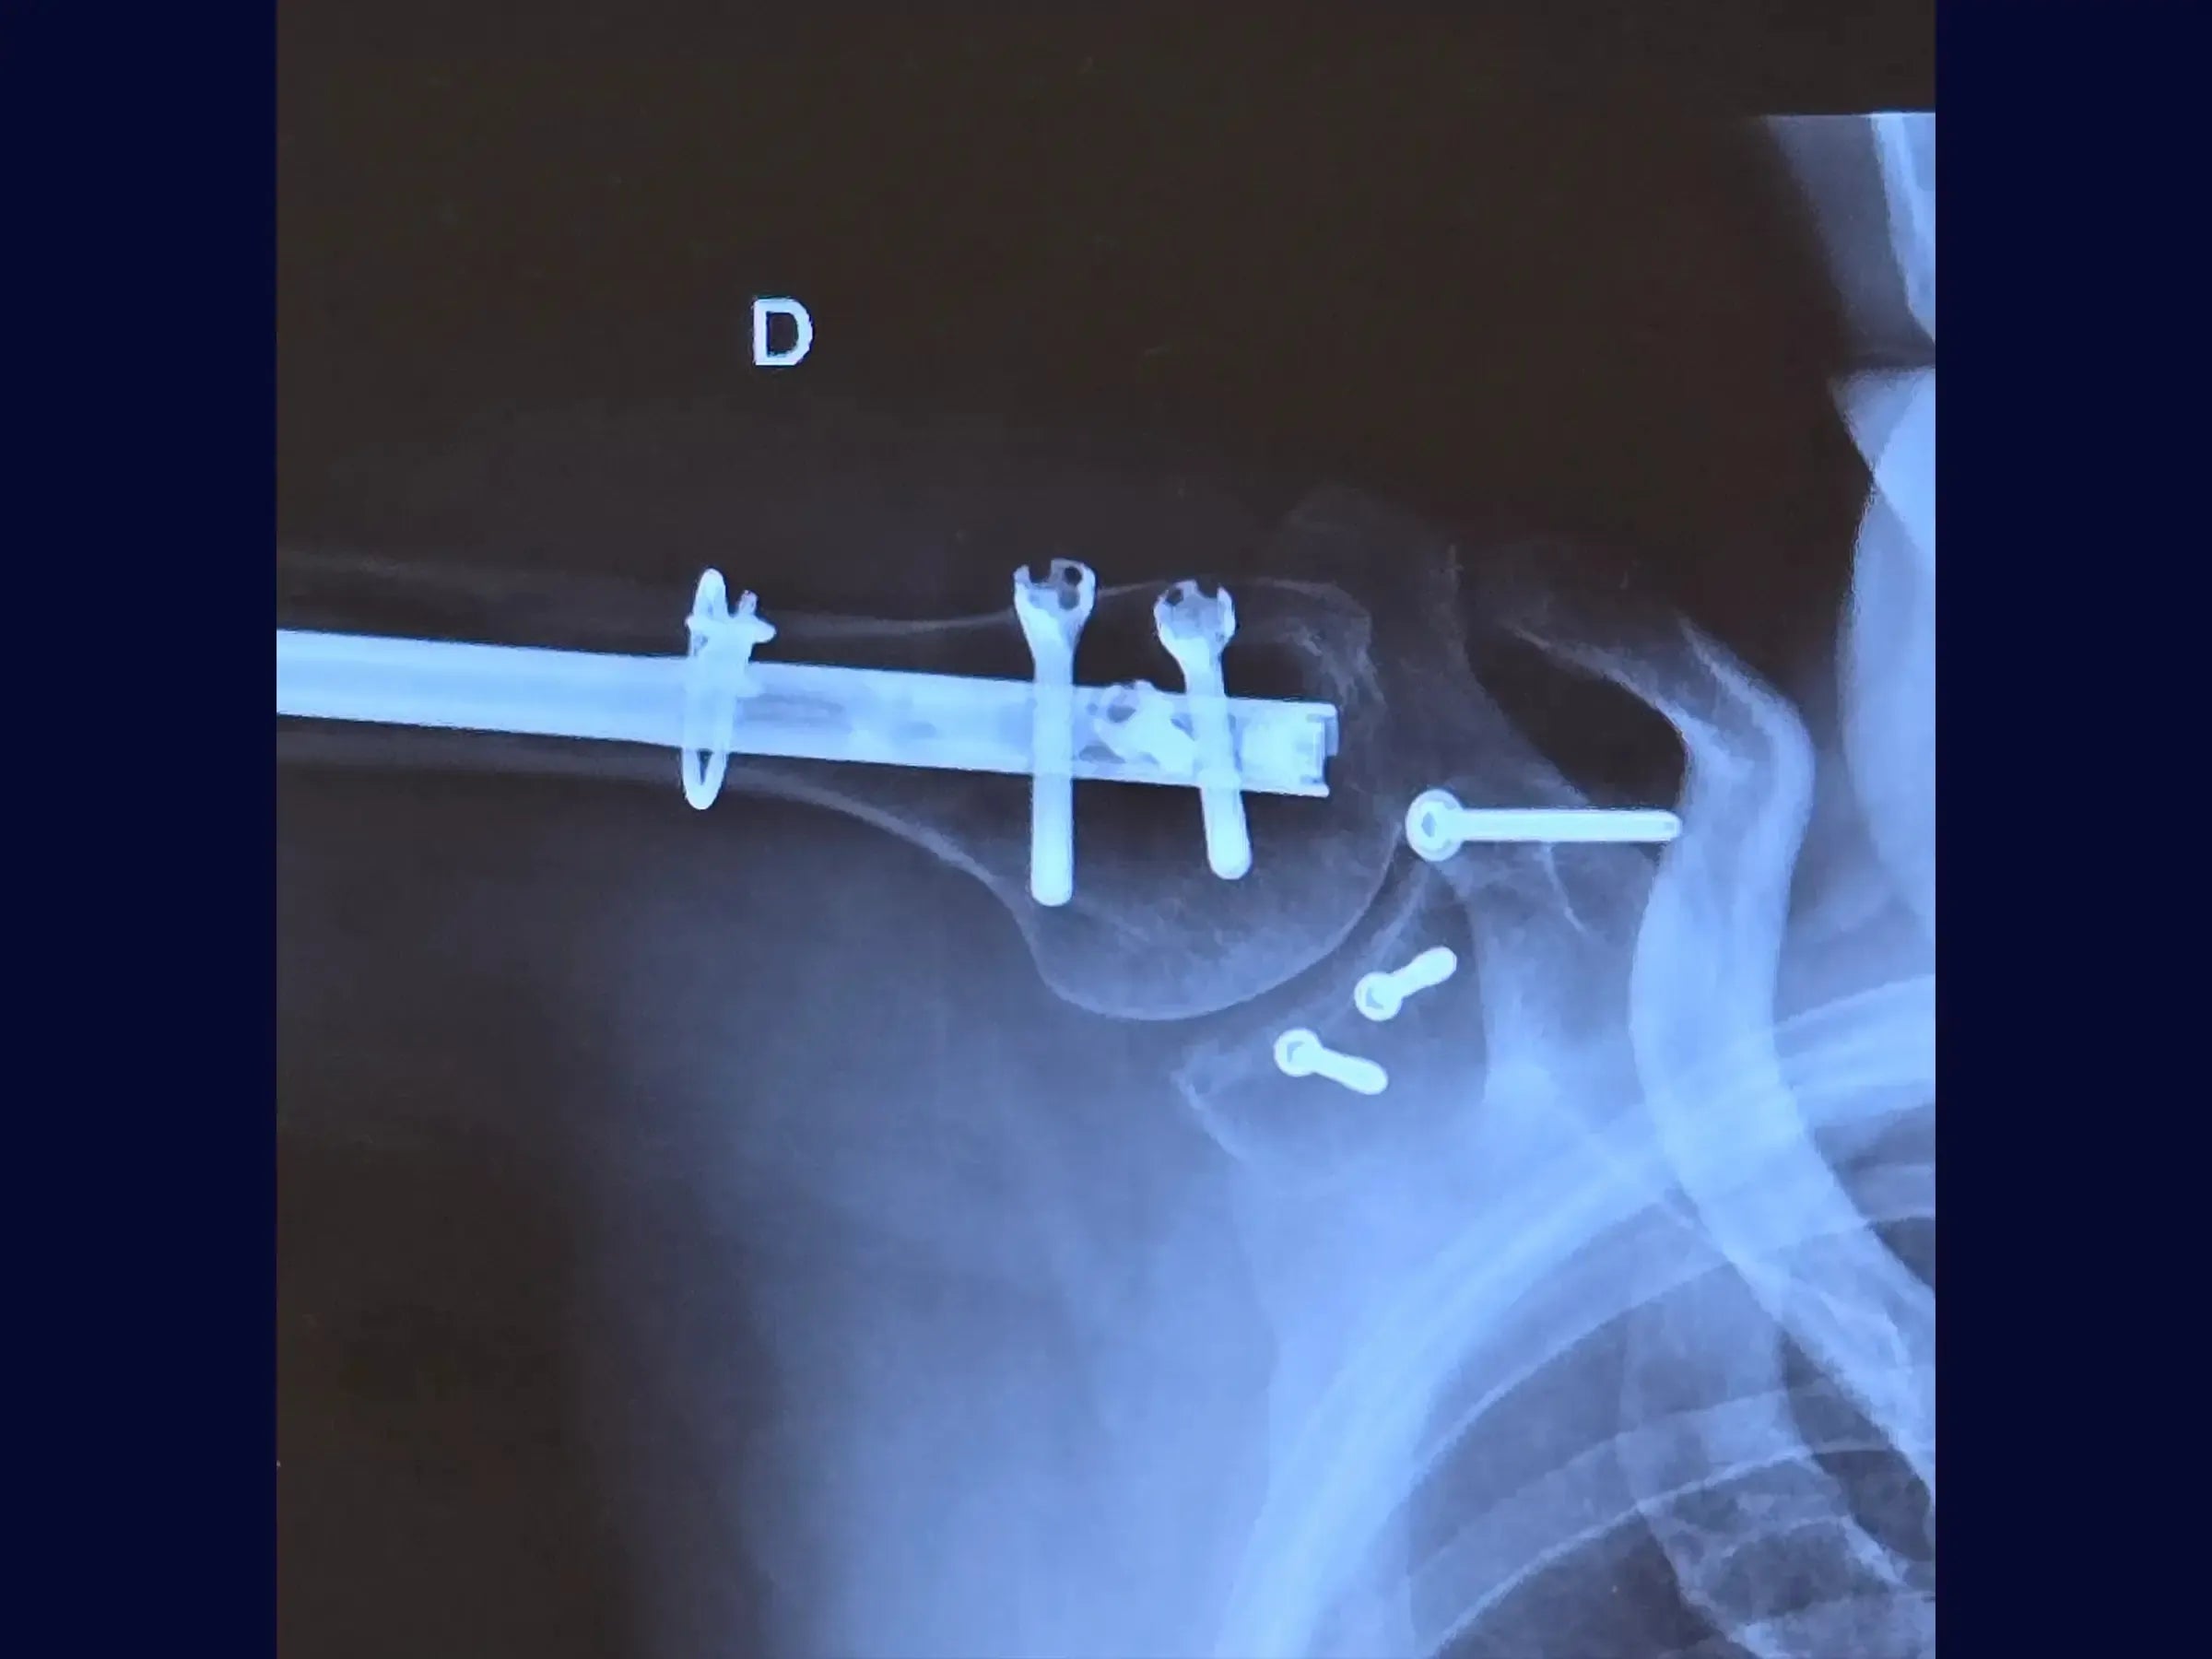

- Osteossíntese com haste intramedular e cerclagem no úmero.

- Fixação com parafusos na glenoide e coracoide.

- Reconstrução Segmentar do Úmero: Abordagem sistemática para identificação dos vértices da fratura, redução do segmento proximal e fixação com haste intramedular e parafusos proximais, complementada por cerclagem, para estabilidade e restauração anatômica.

- Fixação Precisa da Glenoide: Técnica de incisão e separação do subescapular da cápsula articular para exposição e redução do fragmento da glenoide, com inserção de fios guia e parafusos para assegurar a congruência articular e estabilidade.

- Estabilização do Coracoide: Demonstração da fixação do processo coracoide, preso ao tendão conjunto, com parafuso de compressão.

- Fechamento Anatômico e Prevenção de Complicações: Protocolos de sutura da cápsula e subescapular, e fechamento do acesso deltopeitoral para minimizar sangramento pós-operatório e hematoma, otimizando o resultado funcional.